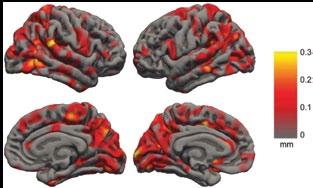

division heads division heads

Professor Alan Connelly is an NHMRC Principal Research Fellow. He is the Co-Division Head of the Imaging Division, and Head of the Advanced MRI Development group. He also heads the MRI imaging Facility at the Florey Austin (including two researchonly 3T MRI scanners) and the Florey Parkville Small Animal Imaging Facility. Prof Connelly is a development MRI physicist whose work has encompassed a range of MR methods, with current focus primarily on diffusion and perfusion MRI and their application to the investigation of epilepsy, stroke, and cognitive function. His group is internationally recognised as leaders in the field of diffusion MRI fibre tractography, and has developed novel methods to characterise the complex white matter fibre connections in the brain. He has published widely in magnetic resonance, general scientific, and neuroscientific journals, and is a member of the editorial board of Epilepsia.